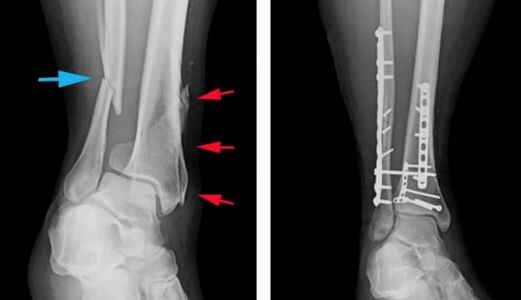

Переломы костей: ускорьте реабилитацию с тепловыми методами